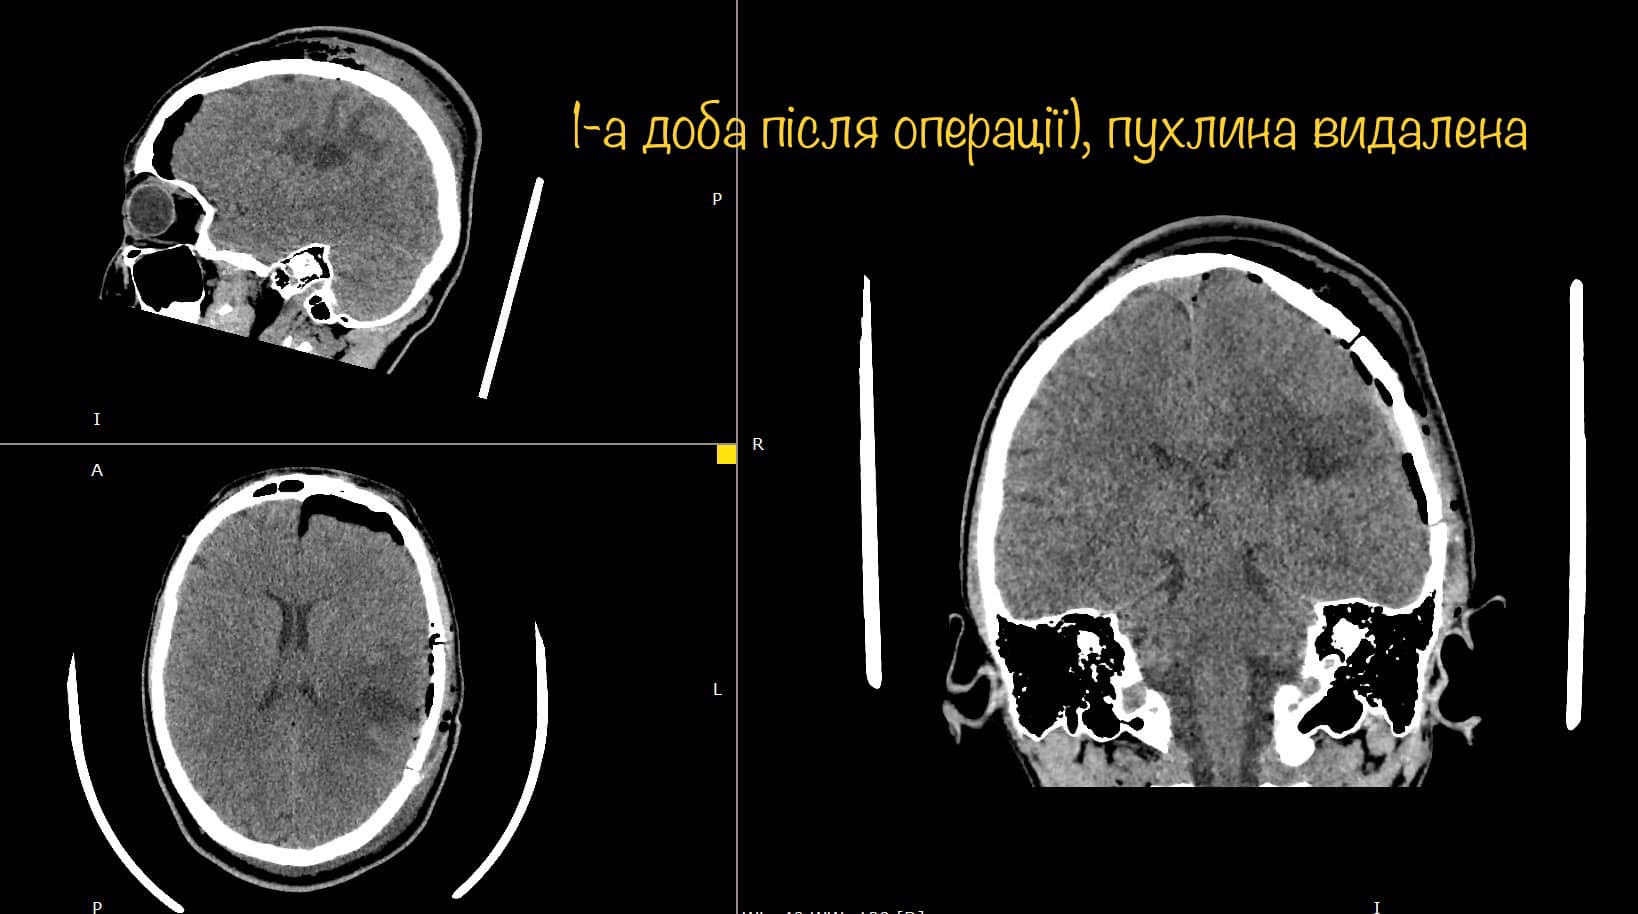

На МРТ виявили пухлину головного мозку з крововиливом в лівій домінуючій (важливішій) півкулі, в якій, власне, окрім центрів, які рухають кінцівками однієї половини тіла, розташований дуже важливий центр мови.

Саме тому єдиний варіант врятувати здатність розмовляти можна тільки провівши таке втручання у свідомості. Тобто під час операції на головному мозку потрібно розбудити пацієнта, а ще знайти центр мови, який у кожного з нас розташований по-своєму, а тоді видалити пухлину за короткий час пробудження (близько години). І після цього знову ввести в наркоз.

І хоча пухлина, як розповідає Михайло Ловга, знаходилась всього в кількох міліметрах від центру мови, і лікарі ледве-ледве знайшли безпечну ділянку мозку, через яку вдалось видалити пухлину – результат лікування чудовий. Діана вже через годину після операції вільно розмовляє, звичайно рухає усіма кінцівка і ні на що не скаржиться.